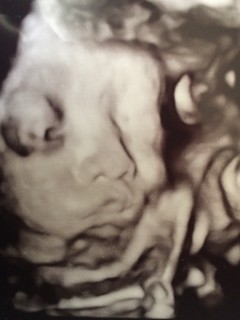

写真:32w5d:BuuChanさん:腕が太い?

「ねんね」のポーズで、自分の腕を枕に目をつぶって寝ています。